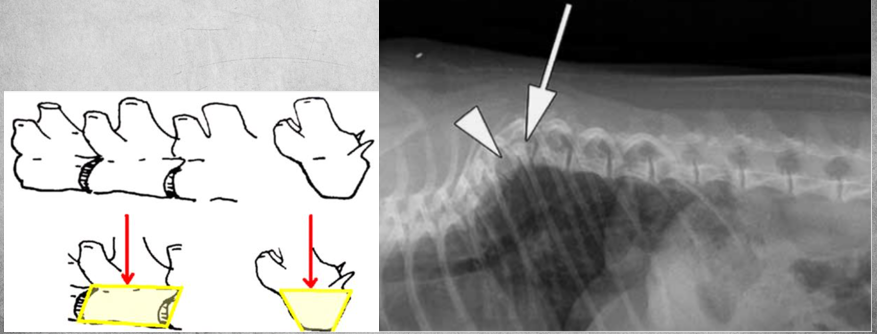

17

identify anomaly

Hemivertebra

Failure of formation of a part of the vertebral body. The vertebra is missing bone part ventrally or dorsally.

Seen in Lateral view, Wedge shape.

More common in brachys but found in others as well. Can cause pain.

18

A

block vertebrae so fusion of two vertebra that should normally be separate vertebrae. (left image)

how to tell if its fusion or loss of intervertebral disc?

Check the margin, is there any time of delineation? (right image)